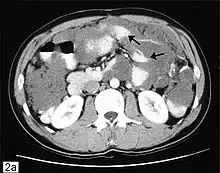

CT scanning is preferred to assess the extent of the tumor in the abdominopelvic cavity, though magnetic resonance imaging can also be used.[28] CT scanning can also be useful for finding omental caking or differentiating fluid from solid tumor in the abdomen, especially in low malignant potential tumors. However, it may not detect smaller tumors. Sometimes, a chest x-ray is used to detect metastases in the chest or pleural effusion. Another test for metastatic disease, though it is infrequently used, is a barium enema, which can show if the rectosigmoid colon is involved in the disease. Positron emission tomography, bone scans, and paracentesis are of limited use; in fact, paracentesis can cause metastases to form at the needle insertion site and may not provide useful results.[29] However, paracentesis can be used in cases where there is no pelvic mass and ascites is still present.[29] A physician suspecting ovarian cancer may also perform mammography or an endometrial biopsy (in the case of abnormal bleeding) to assess the possibility of breast malignancies and endometrial malignancy, respectively. Vaginal ultrasonography is often the first-line imaging study performed when an adnexal mass is found. Several characteristics of an adnexal mass indicate ovarian malignancy; they usually are solid, irregular, multilocular, and/or large; and they typically have papillary features, central vessels, and/or irregular internal septations.[31] However, SCST has no definitive characteristics on radiographic study.[33]

In advanced cancers, where complete removal is not an option, as much tumor as possible is removed in a procedure called debulking surgery. This surgery is not always successful, and is less likely to be successful in women with extensive metastases in the peritoneum, stage- IV disease, cancer in the transverse fissure of the liver, mesentery, or diaphragm, and large areas of ascites. Debulking surgery has usually only been done once[28] but a recent study has shown a longer overall survival in recurrent ovarian cancer when surgery combined with chemotherapy was performed compared to treatment with chemotherapy alone.[95] Computed tomography (abdominal CT) is often used to assess if primary debulking surgery is possible, but low certainty evidence also suggests fluorodeoxyglucose‐18 (FDG) PET/CT and MRI may be useful as an addition for assessing macroscopic incomplete debulking.[96] More complete debulking is associated with better outcomes: women with no macroscopic evidence of disease after debulking have a median survival of 39 months, as opposed to 17 months with less complete surgery.[26] By removing metastases, many cells that are resistant to chemotherapy are removed, and any clumps of cells that have died are also removed. This allows chemotherapy to better reach the remaining cancer cells, which are more likely to be fast-growing and therefore chemosensitive.[29]